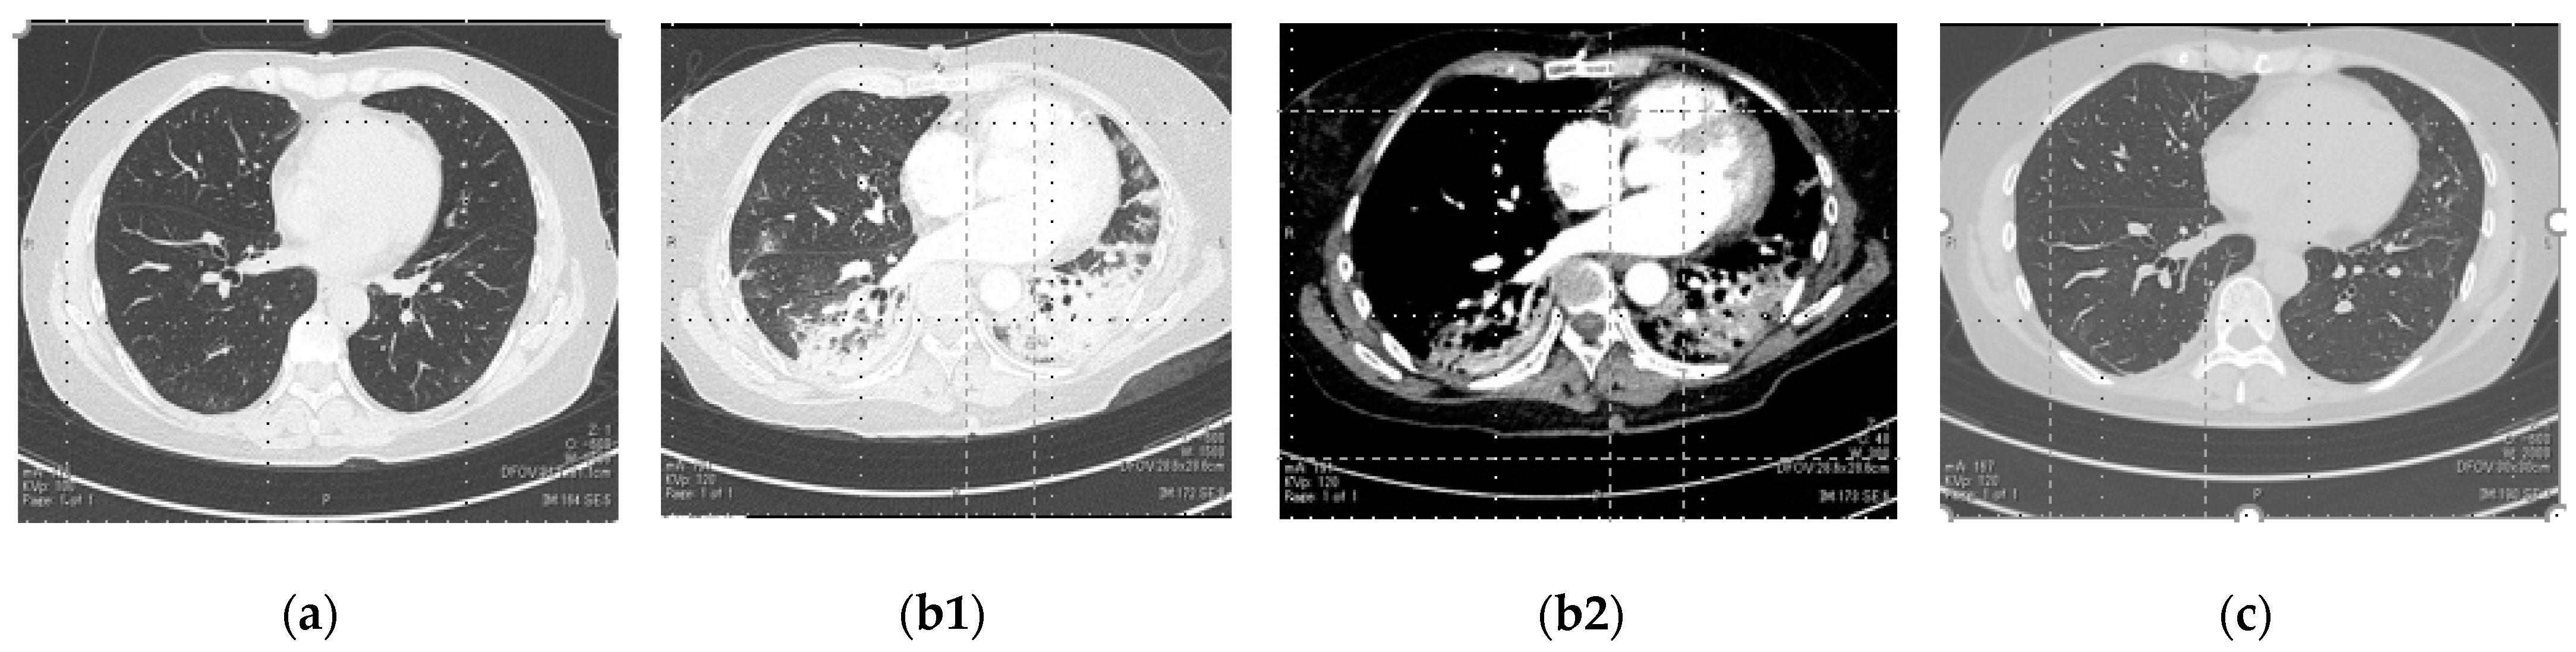

A chest computed tomography (CT) scan on admission did not show ground-glass opacities (GGOs) in her lungs (Figure 1a). The vital signs of the patient included a heart rate of 108 beats/min, a respiratory rate of 20 breaths/min, an axillary temperature of 38.3 °C, oxygen saturation (SpO2) in ambient air of 94% (Figure 2), and blood pressure of 120/79 mmHg. These were considered only mild diseases. Azithromycin (500 mg/day), ciclesonide (200 µg inhaler; 2 inhalations per day), nafamostat mesylate (40 mg/day), and favipiravir (3600 mg on the first day, 1600 mg thereafter) were administered. Despite these treatments, the patient’s clinical status was not improved on day 2. Specifically, her high fever and exhaustion persisted. Furthermore, the CRP and urinary B2M levels were elevated. Because of the lack of improvement in clinical outcomes, 400 mg of TCZ was given intravenously. The fever disappeared. However, on day 4, a disturbance of consciousness, associated with tachypnea, appeared suddenly. Her vital signs worsened to an SpO2 of 70% in ambient air and blood pressure of 70 mmHg (systolic). Her enhanced chest CT image showed consolidations in both lower lobes of her lungs and GGOs around the consolidation at this point (Figure 1(b1)). There was no proof of a pulmonary embolism (Figure 1(b2)). The patient was immediately brought to the ICU with the administration of adrenalin for endotracheal intubation and mechanical ventilation. In addition, the drugs already given were modified as follows: levofloxacin at 500 mg (for 4 days), heparin sodium at 15,000 units (for 4 days), dexamethasone at 6.6 mg (for 10 days), and remdesivir (200 mg loading dose on day 1 followed by 100 mg daily for up to 3 additional days). The ventilator was set to positive airway pressure (initial positive inspiratory pressure of 22 cm H2O and an expiratory positive airway pressure of 5 cm H2O) under the condition of the fraction of inspiratory oxygen (FIO2) of 0.6. Arterial blood gas analysis reported an arterial O2 tension (PaO2) of 74.1 Torr and an arterial CO2 tension (PaCO2) of 46.3 Torr.

The consolidation disappeared on the CT after extubation (Figure 1c). The patient’s LDH, CRP, and urinary B2M decreased. The patient’s ferritin and D-dimer levels were not extremely in excess of the normal range in the hospital (Table 1). Only Gal-9 was increased two days (day 2 and 6) after exacerbation. Gal-9 was measured using a human Gal-9 ELISA kit (GalPharma Co., Ltd., Takamatsu, Japan) as described [9]. It was also on the rise when admitted and had a second increase on day 6 (Figure 4). Gal-9 decreased with the improvement in the clinical outcomes. On day 16, the patient was discharged.

A 53-year-old Japanese COVID-19 patient woman was admitted and given four kinds of drugs (antibiotics, protease inhibitors, inhalant corticosteroids, and antivirals). However, there was no response in terms of symptom alleviation and high fever, cough, fatigue, and loss of appetite persisted. TCZ was administered to improve these clinical findings. Although TCZ demonstrated an antipyretic effect and an improvement in the patient’s laboratory data, the consolidation shadow suddenly appeared in both lungs, and SpO2 was lowered. This was consistent with COVID-19 pneumonia rather than a pulmonary embolism, because the contrast enhancement CT did not show pulmonary artery obstruction. Seven days after she was connected to the ventilator (11th day after hospitalization), her respiratory condition improved.

Figure 1. Computed tomography (CT) images of the patient’s lungs on day 0 (a), day 5 (b1,b2), and day 16 (c) with a: no abnormality; (b1): indicates consolidation and GGOs in bilateral lungs; (b2): indicates pulmonary artery contrast-enhanced findings without defect; and (c): indicates the disappearance of consolidation and GGOs.